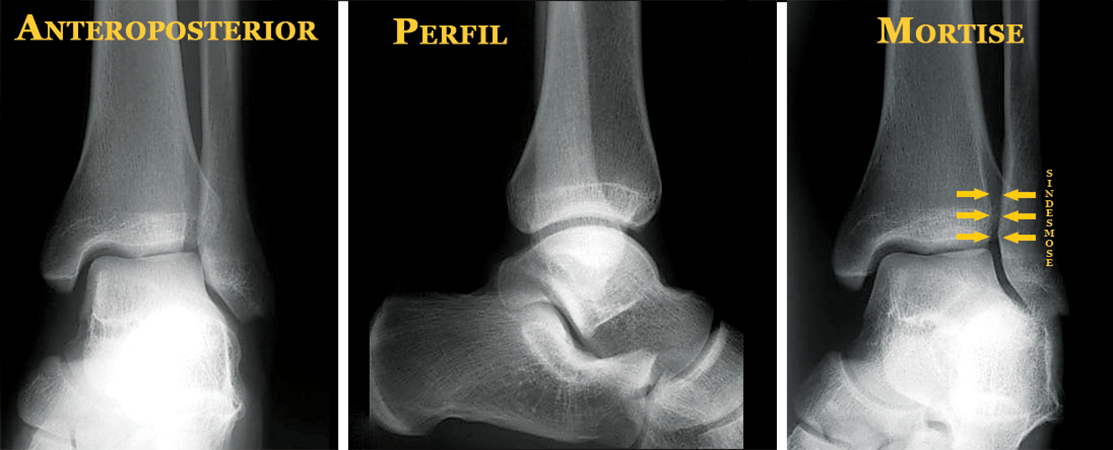

É imprescindível o exame radiológico bilateral, comparativo. As três incidências básicas são: anteroposterior, perfil e mortise (obliqua com rotação interna de 15°-20°).

O raio X fornece informações importantes para o tratamento, como a localização e a extensão do(s) traço(s) da fratura, o desvio dos fragmentos ósseos e as lesões ligamentares associadas, principalmente a lesão da articulação tibiofibular (sindesmose).

A lesão ou abertura da articulação tibiofibular (sindesmose) deve ser diagnosticada e tratada cirurgicamente. Neste caso, utiliza-se um longo parafuso ou mecanismo de contenção que mantenha a “pinça” articular fechada e estável até a completa cicatrização ligamentar.